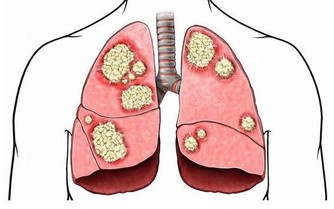

如果視力模糊,或有糖尿病足,或有糖尿病並發心髒病之類的情況就不適合強度運動,